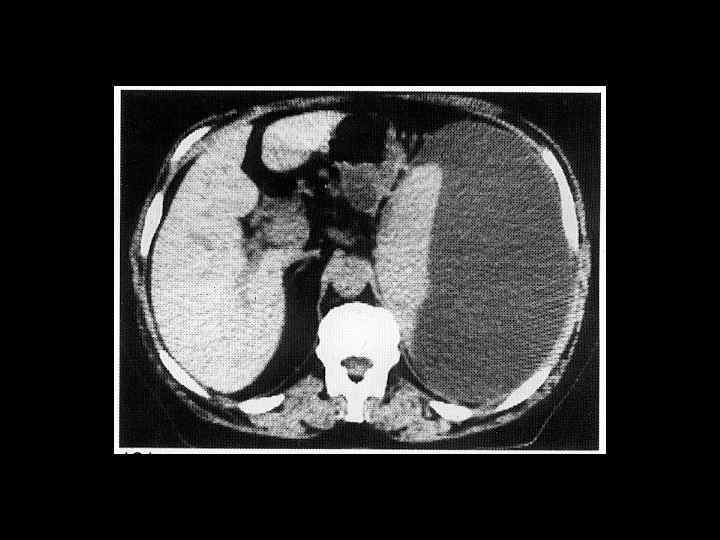

АКТУАЛЬНЫЕ ВОПРОСЫ РЕНТГЕНОЛОГИИ ЛУЧЕВАЯ ДИАГНОСТИКА ЗАБОЛЕВАНИЙ СЕЛЕЗЕНКИ Кисты и абсцессы селезенки